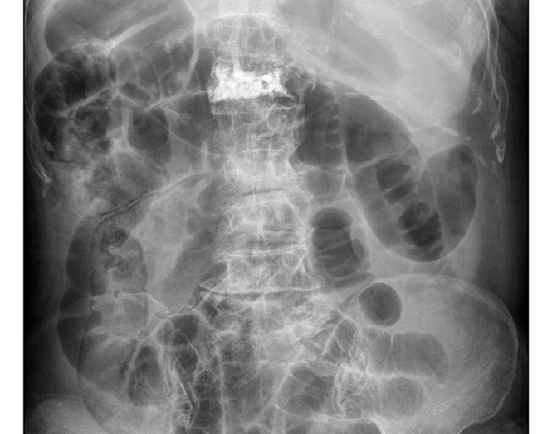

本研究对象为一名青少年腹胀个案,接受了包含初步评估、针对性VM技术(重点关注大肠、肠系膜及相关筋膜结构)以及两次治疗后的再评估之结构化治疗计划。进展监测指标包括触诊发现、腹围测量及主观症状评分。

个案无已知胃肠疾病诊断,实验室检验与影像学检查结果正常。

评估大肠(升结肠、横结肠、降结肠)、乙状结肠、小肠、肠系膜、回盲瓣及悬吊韧带的内脏活动度与动力性